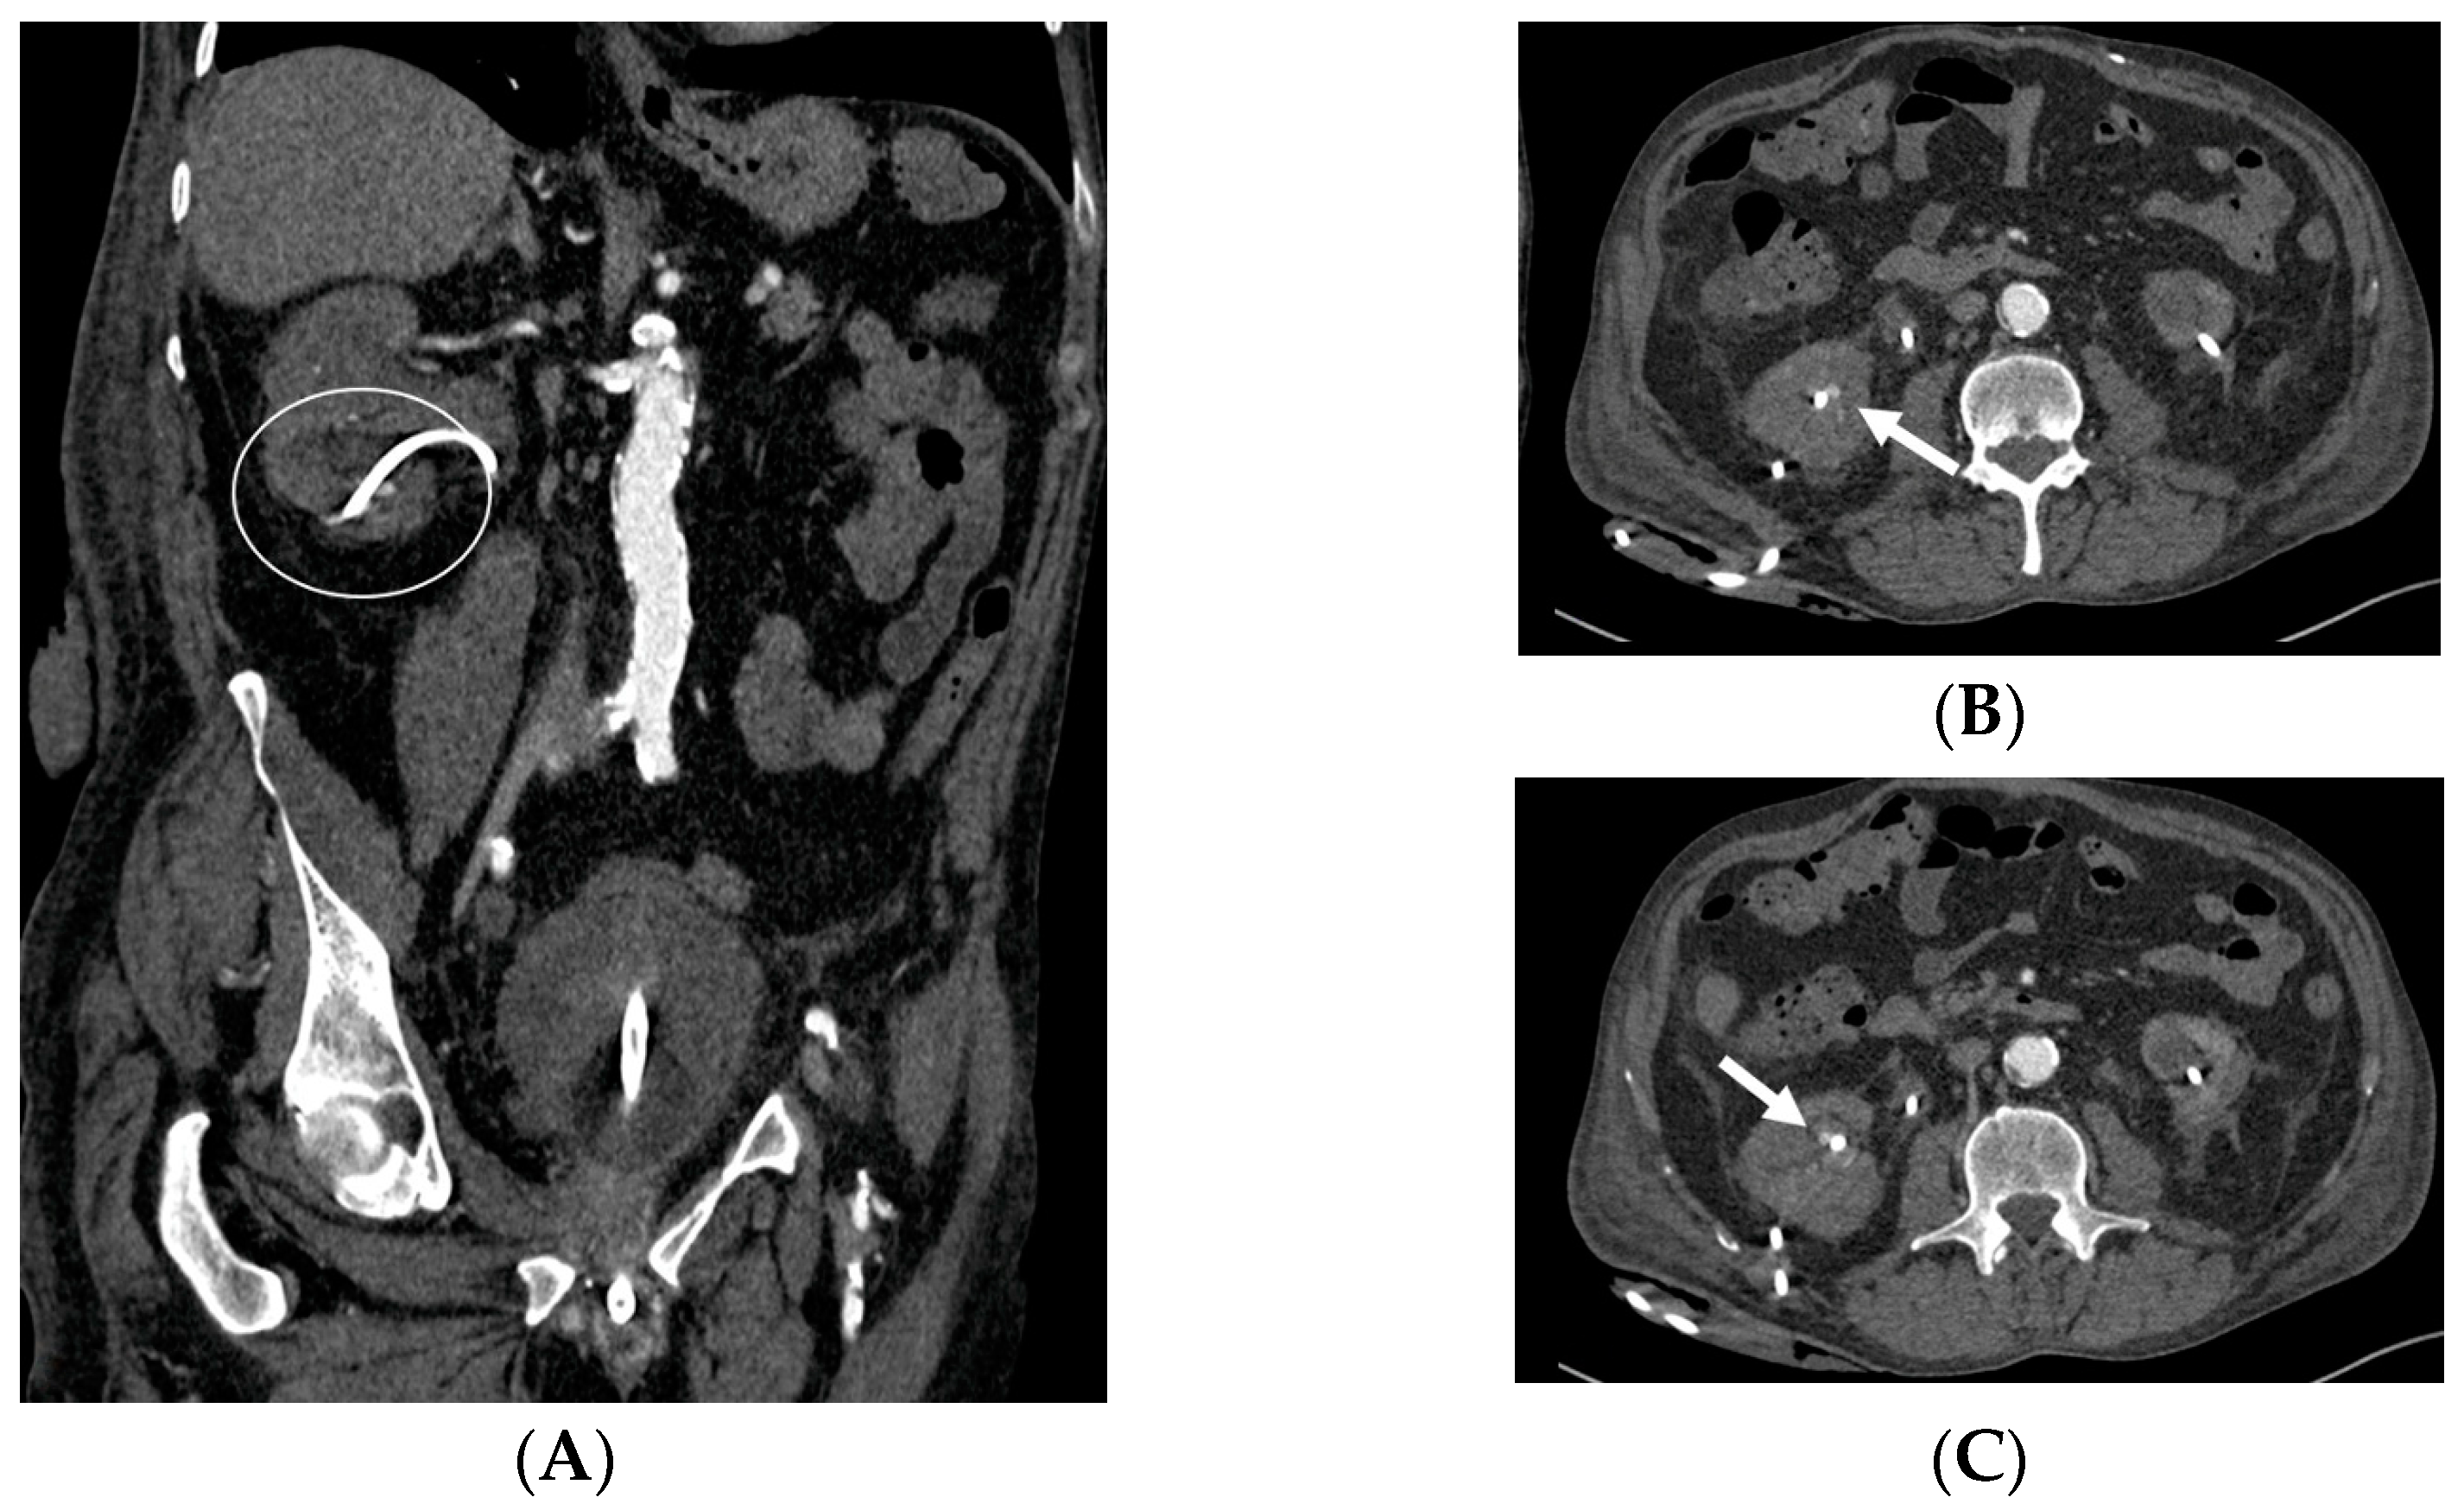

- Malposition: The malposition of a stent is defined as an incorrect position relative to initial placement, while displacement presents a subsequent occurrence in a device that was previously located in the correct position. A stent improperly positioned might assume a sub-pyelic position when the proximal end fails to reach the renal pelvis and a supravesical position when the distal end is detected within the ureter. The origins of this complication predominantly stem from the placement technique, whether it be endoscopy- or fluoroscopy-guided insertion. This underscores the need to verify the accurate positioning of the stent post-placement. Ensuring an adequate length is essential to reduce the occurrence of this complication (Figure 2, Figure 3, Figure 4, Figure 5 and Figure 6) [21,22].

- Stent Knotting: It is a rare complication. Most of these knots involve the proximal end of the stent near the coil, but every portion can be affected [27,28]. Previous reports have attributed knot formation to the excessive length of the stent, stent shape (double-J or multicoil), and flexibility or anatomical abnormalities, such as cystocele and ileal conduits. An abdominal X-ray and, especially, a CT scan are more sensitive than other imaging modalities in identifying a ruptured or knotted stent as well as its migration (Figure 7) [29,30].